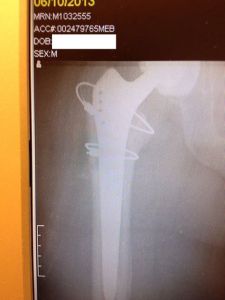

I put up with the pain until April 2013 and then decided I had to take action. I was desperate. The constant pain led to severe depression. At this point, I knew that I needed to find a new doctor; but how? I believe that one of the biggest problems in health care today is that there really are no resources available to allow a patient to intelligently select a doctor. No central clearing houses with ratings. Everything is by word of mouth. I hate to bother friends with questions related to their work, but not knowing what else to do, I finally turned to some of my friends who are doctors. I said that I was at my wit’s end and that I needed help. One friend passed me to a colleague who is an orthopedic pathologist, who recommended Dr. Marc Hungerford at Mercy Hospital in Baltimore. I wish I could put into words how much better my experience with Dr. Hungerford and his staff was, compared to my first surgeon. The difference was so great that expressions such as, “different as night and day” do not do it justice. Dr. Hungerford looked at the X-rays and knew immediately why I had the pain; the prosthesis was loose and was impinging on the side of the femur, which was causing the pain. When he showed us the problem on the X-rays it was obvious to both me and to my wife…why my first surgeon could not see this, and why he let me suffer for so long, I don’t know.

Anyway, in June Dr. Hungerford performed the revision. Everything went well and I felt better immediately. I was able to stop taking prescription pain medication after only two weeks. I soon felt good enough that, even though I was on a walker and wearing a hip brace, I could go out for a walk around the neighborhood each day. It was liberating! Unfortunately, with my head now clear, working at home was difficult. I missed the interaction with my coworkers and didn’t need the quiet to concentrate and focus. Despite the walker and hip brace, I felt I needed to go into the office at least once or twice a week to maintain my sanity. The memories of this time are not colored gray, they are full of sunlight and blue skies. In late July, when I went from a walker to a cane, I resumed driving and went back to work full time…I believe that was the beginning of my rebirth.